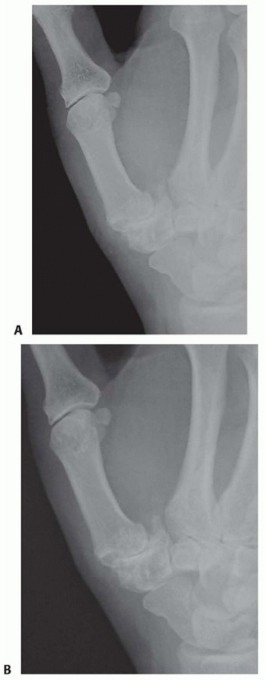

Radiographic Assessment and Staging

Standard posteroanterior (PA) and lateral views of the hand are insufficient for evaluating the basilar joint due to its 30-degree pronated position relative to the rest of the carpus. We require dedicated thumb views: a pronated AP (Robert view), a true lateral of the thumb, and a 30-degree PA stress view. The stress view, obtained by having the patient forcefully press the tips of their thumbs together, is invaluable for unmasking dynamic dorsal subluxation and assessing the competence of the capsuloligamentous envelope.

Image

We utilize the Eaton and Littler radiographic staging system to guide our surgical approach. However, the operating surgeon must always critically evaluate the scaphotrapezial-trapezoidal (STT) joint. As emphasized by Tomaino et al., failure to recognize and address STT arthritis (Stage V disease) is a primary cause of persistent postoperative pain following isolated CMC procedures.

• Stage I: Normal-appearing articular surfaces or slight widening of the joint space, indicative of synovitis and early ligamentous laxity.

• Stage II: Joint space narrowing with the formation of marginal osteophytes smaller than 2 mm.

• Stage III: Advanced joint space narrowing, subchondral sclerosis, and osteophytes larger than 2 mm.

• Stage IV: Pan-trapezial disease involving advanced arthrosis of both the TM joint and the scaphotrapezial joint.

• Stage V (Tomaino modification): Stage IV appearance with the addition of advanced narrowing, sclerosis, or osteophytes within the scaphotrapezoid articulation.